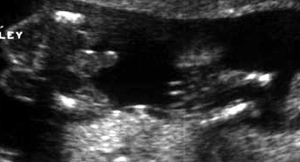

ثانيا : البنت

الاسبوع ال16

الاسبوع ال17

الاسبوع ال18

الاسبوع ال19

الاسبوع ال20